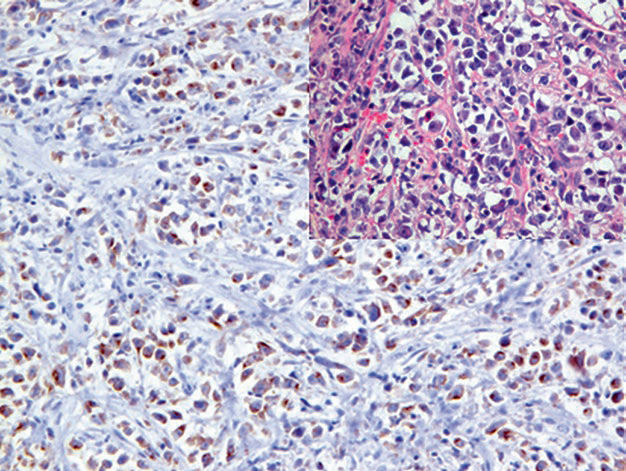

CD30参与细胞转化、抗体作用、凋亡等方面的调节,正常情况下表达于活化的B、T、NK细胞。除霍奇金淋巴瘤和某些其他类型淋巴瘤外,CD30还是间变性大细胞淋巴瘤的诊断标记。关于CD30的更多细节,本系列文章后续会有详述。

图3. 间变性大细胞淋巴瘤,CD30弥漫阳性。

阳性表达模式:细胞膜/细胞质

推荐阳性质控组织:阑尾/扁桃体